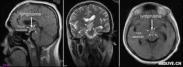

中耳癌為發(fā)生于中耳的少見惡性癌腫,多為原發(fā)。中耳癌的誘因,很可能是中耳的長期感染,據(jù)統(tǒng)計(jì),多數(shù)中耳癌患者有慢性化膿性中耳炎的病史。其發(fā)病年齡多為40~60歲,本病病理是以鱗狀上皮細(xì)胞癌最常見,基底細(xì)胞癌和腺癌在中耳很少見。